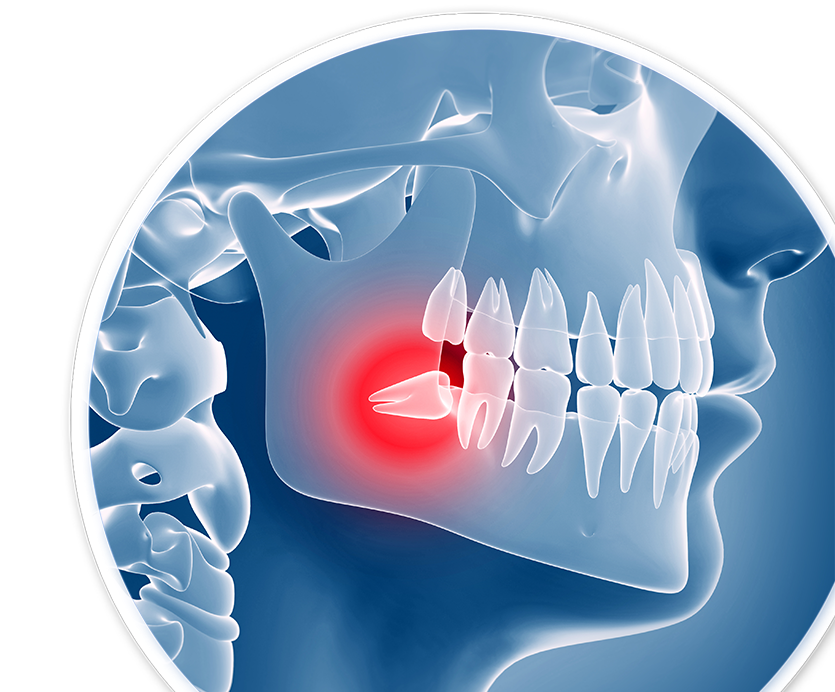

Impacted Wisdom Teeth:

A Common Problem

Nine out of every 10 patients have at least one impacted wisdom tooth, according to the American Academy of Oral and Maxillofacial Surgeons.

Before taking any steps, our oral surgeons in Cocoa, FL, will first assess your mouth using panoramic X-rays. Our advanced imaging technology provides detailed information that is not captured in a typical dental X-ray. Using this information, our doctors are able to precisely plan your surgery and avoid nearby sensitive tissue, such as important nerves in the jaw.